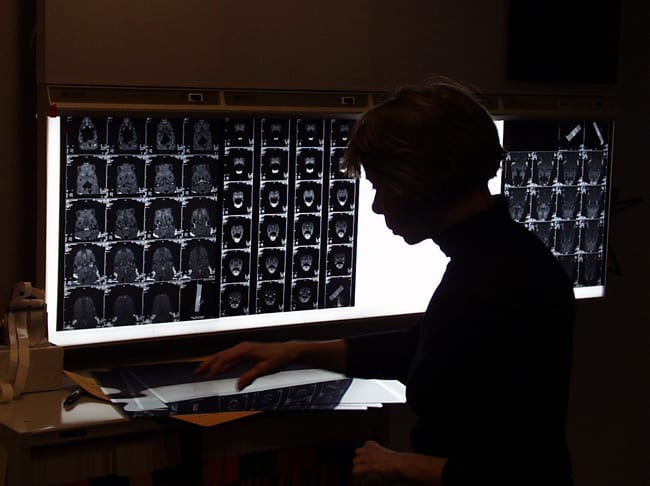

The experiments involve CT scanning the carcasses before and after the blasts and then dissecting the specimens to examine, in some cases microscopically, every major organ to detect any trauma related to the blast waves, which are recorded by sensors. By comparing the pressure wave readings recorded by the sensors with the CT scans and injury summaries, the researchers can determine the relationships between the pressures the animals received and the damage they sustained.

- WHOI biologist Darlene Keten examines CT images of turtle bodies, taken before and after each experiment, to determine the location and magnitude of injuries from blast exposures. (Courtesy of Darlene Ketten, Woods Hole Oceanographic Institution)